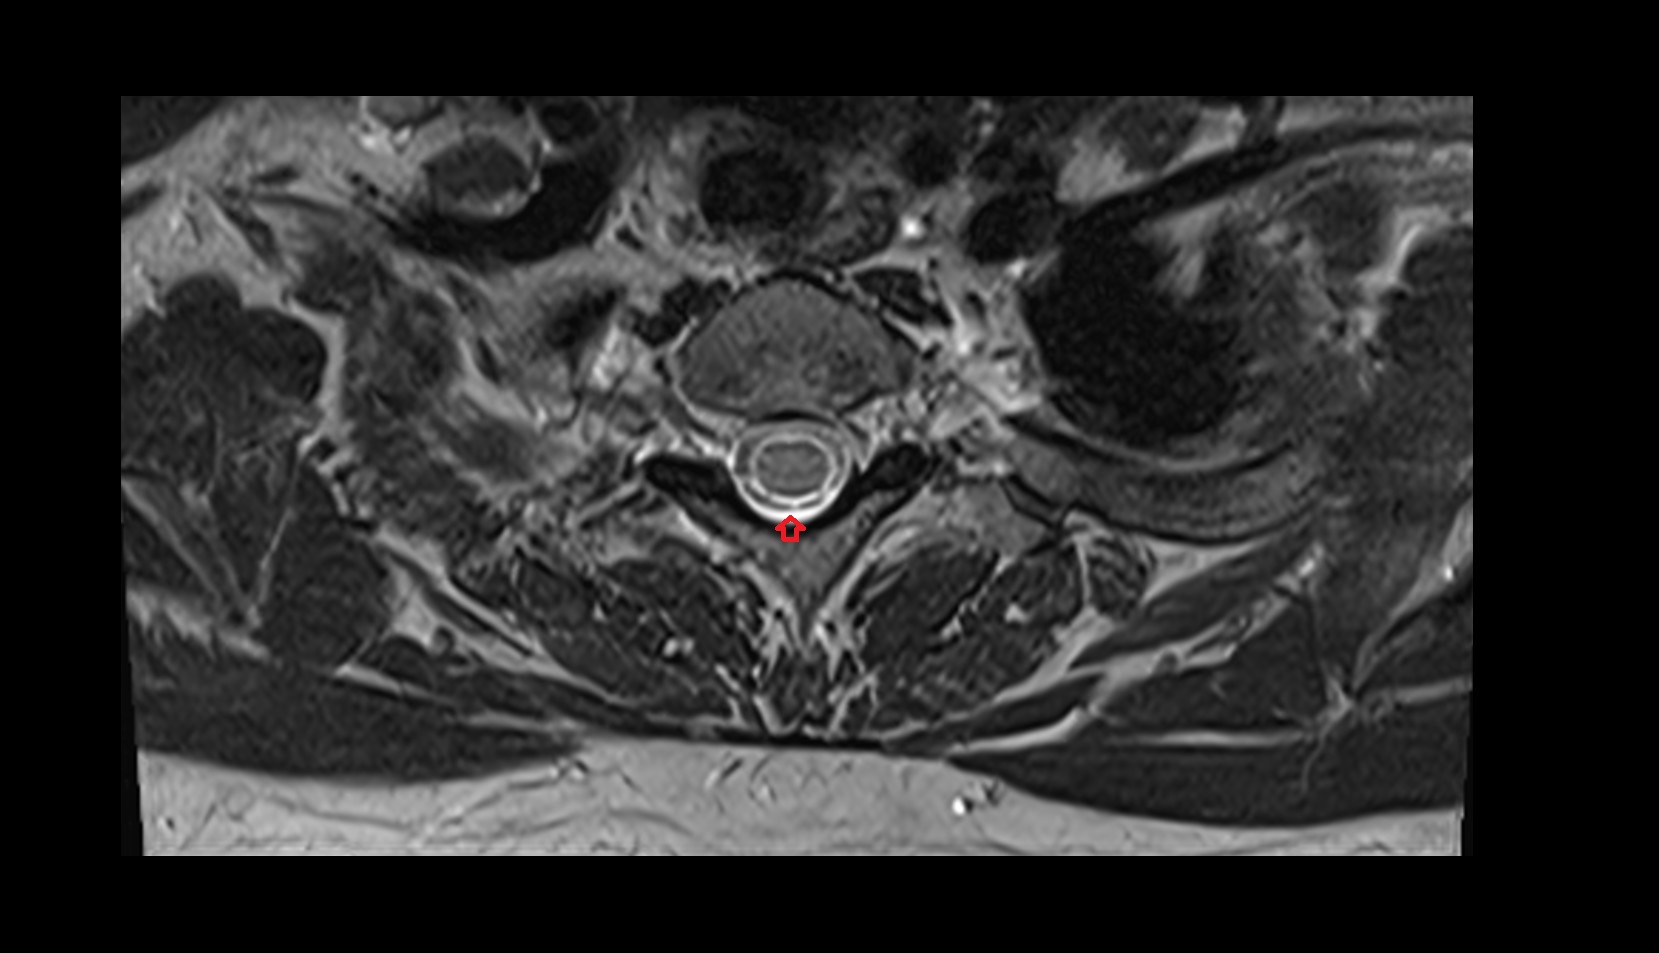

- Cauda equina

- Conus medullaris